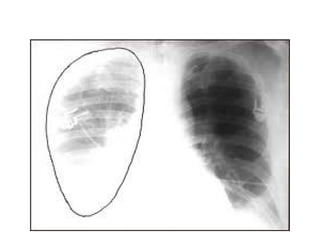

DERRAME LIBRE

• Se produce una sombra de la misma densidad del corazon,

que se localiza inicialmente en el angulo costofrenico

posterior, tiene concavidad superior siendo mas alta en la

region lateral que medial

• Para obliterar los angulos costofrenicos posterior y lateral se

requieren 75 y 175 ml de liquido respectivamente